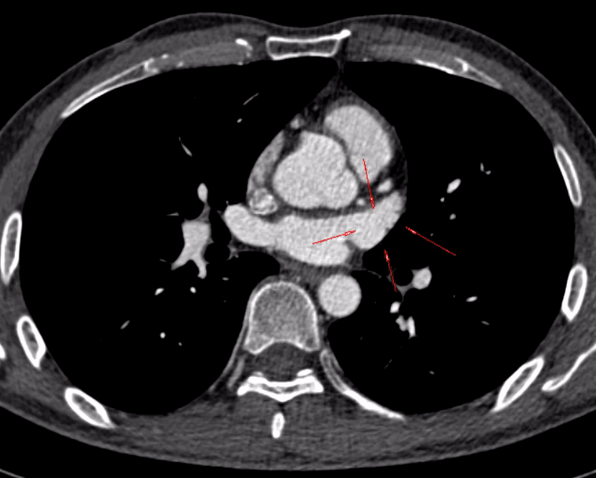

医务人员在为胡先生行左心房-肺静脉CT造影检查时,看到他的左心耳见斑片状充盈缺损,形象地说就像“鸡翅”缺了一块。这就是典型左心耳血栓的表现。

正常做左心耳在CT造影上形态为鸡翅型最为常见